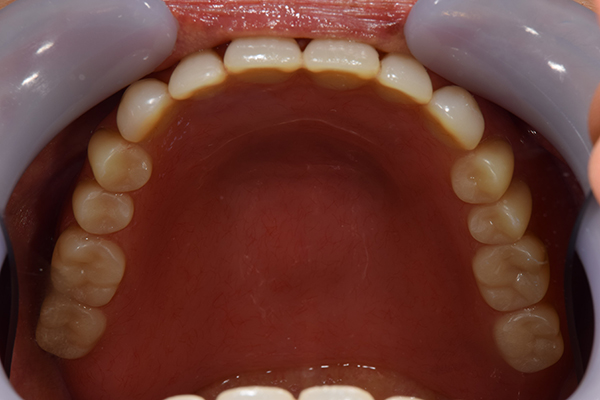

入れ歯をお口の中にいれた状態です。前歯もMTMといって、歯を少し引っ張り出す処置を行なったことで、しっかり残せて、またかぶせ物をしました。

お口の中に入れた状態です。 見た目も最初とほとんど変わることなく作成できました。 維持や吸着に関しても問題ないようでした。

入れ歯を入れた状態のお口の中の写真です。バネも極力目立たないように作成しています。

お口の中に入れた状態です。 非常に見た目もよい出来となりました。 バネがみえないと見栄えが全然ちがいます。